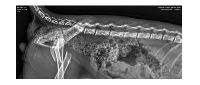

Recentemente adotei um gatinho bebê (2 Meses), e desde o primeiro momento ele mancava muito, mas aparentemente sem dor ou algum tipo de 'dificuldade' além. Imediatamente procurei um veterinário, e através do exame de Raio X descobrimos uma fratura completa que tanto pela idade, quanto pela gravidade da situação, foi considerado um caso urgente com risco de fratura exposta enquanto não é realizado a cirurgia. Como foi uma situação muito inesperada não consigo arcar com os custos sozinha e de forma imediata, pois os custos da cirurgia totalizam aproximadamente R$4.000,00.